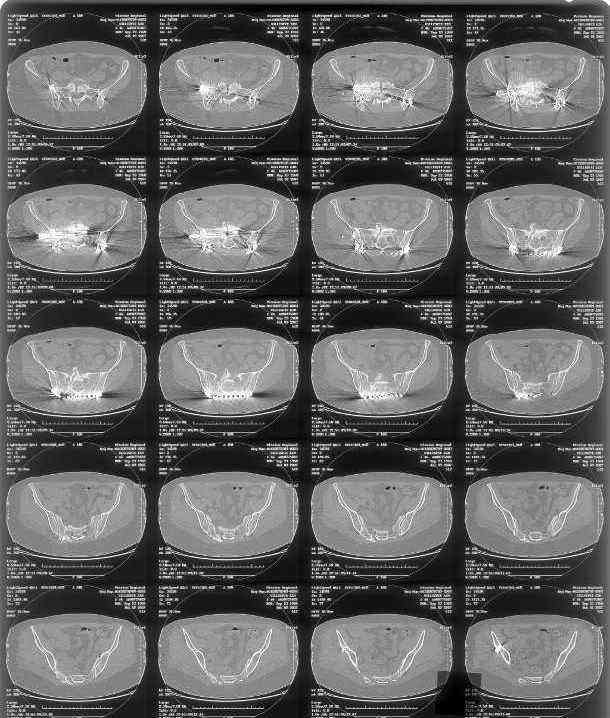

Looking for advice. This is a 48 yo non-smoking female s/p MCC 10 months ago. I do not have the initial injury films. She underwent ORIF as shown on attached file. She is having continued pain in low back/sacral region. Worse with sitting and prolonged walking. Has had pain since surgery. All of her wounds have healed uneventfully. Also has right hip pain laterally. No groin pain. Not aggravated with ROM of the hip. Infection work-up has been negative.

Any thoughts on the broken plate on the pelvic brim and the non-union on the anterior column. Doesn't seem like she's have pain from there.

Suggestions on treatment of sacral nonunion.

I can't see the axial CT images well enough to detail the potential sacral issues....can you magnify them?

Here is a magnified view. Sorry about the quality but the CT was scanned into our system.